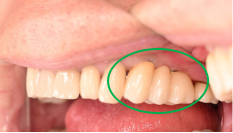

Before

After

2026年2月9日にインプラント埋入手術をし、5月1日に最終的な被せ物を入れました。ブリッジや義歯は、歯がないところに掛かる力を、他の歯が支えることになります。インプラントは、他の歯に負担をかけることはありません。一本欠損になってしまったときは、1本だけインプラントを入れて、他の歯を護り、それ以上歯を失わないことが大切になります。